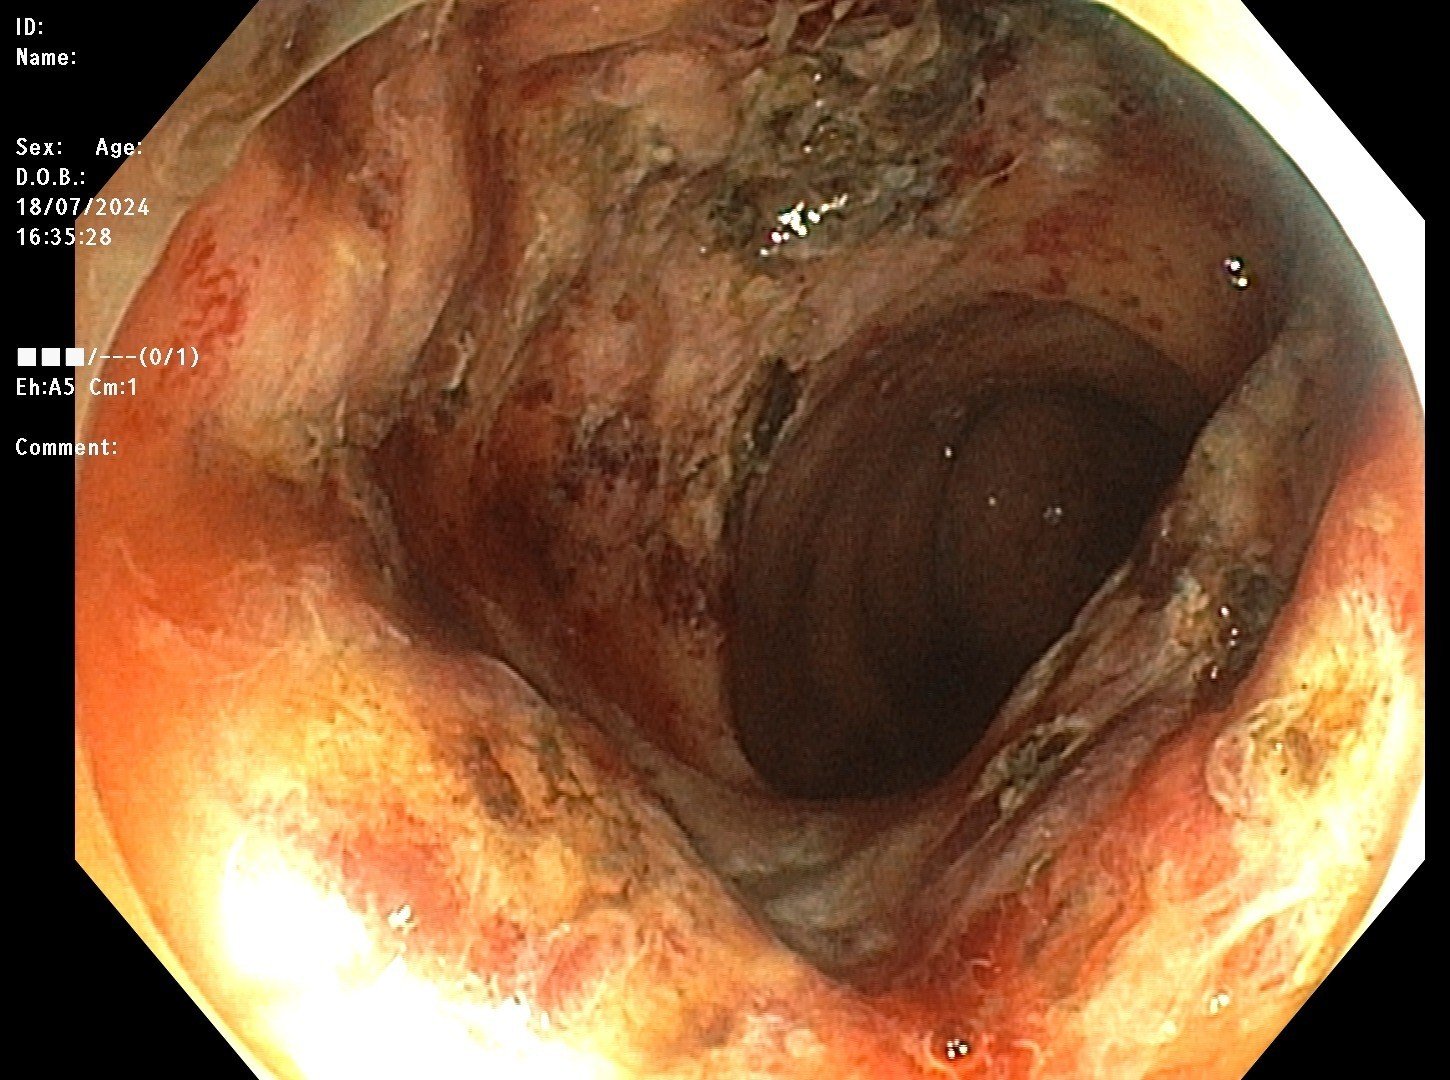

- Hình ảnh sau can thiệp cầm máu, đốt Argon Plasma

Theo BSCKI. Nguyễn Đăng Tuấn – Phó trưởng Khoa Tiêu hóa – Nội soi: Phương pháp cầm máu bằng Argon Plasma có ưu điểm là đông máu không tiếp xúc, sử dụng khí trơ argon phát ra tia plasma, phân bố năng lượng nhiệt lên các mô xung quanh đầu dò để xử lý tổn thương. Nhờ đó cải thiện tối ưu những tổn thương ở mạch máu, cầm máu nhanh, không gây đau đớn, giảm tai biến. Với bệnh nhân trên, xạ trị gây viêm trực tràng dẫn đến chảy máu; nếu người bệnh không được phát hiện và điều trị hiệu quả, có thể gây ra biến chứng nguy hiểm như thiếu máu cấp tính hoặc mạn tính và tử vong.

Ngay sau can thiệp, tình trạng xuất huyết tiêu hóa của người bệnh đã được kiểm soát, không còn chảy máu, người bệnh đã đại tiện phân vàng. Sức khỏe bệnh nhân dần hồi phục và được xuất viện.

Với tổn thương có nhiều mao mạch đang chảy máu thì phương pháp Argon plasma (Argon Plasma Coagulation-APC) là kĩ thuật cầm máu tối ưu. Tại Bệnh viện đa khoa Quốc tế Hải Phòng với đội ngũ chuyên gia, bác sĩ giỏi chuyên môn, giàu kinh nghiệm, làm chủ kỹ thuật đã thực hiện hiệu quả, thường quy trên nhiều ca bệnh, mang lại kết quả điều trị tối ưu, nâng cao chất lượng sống cho người bệnh.